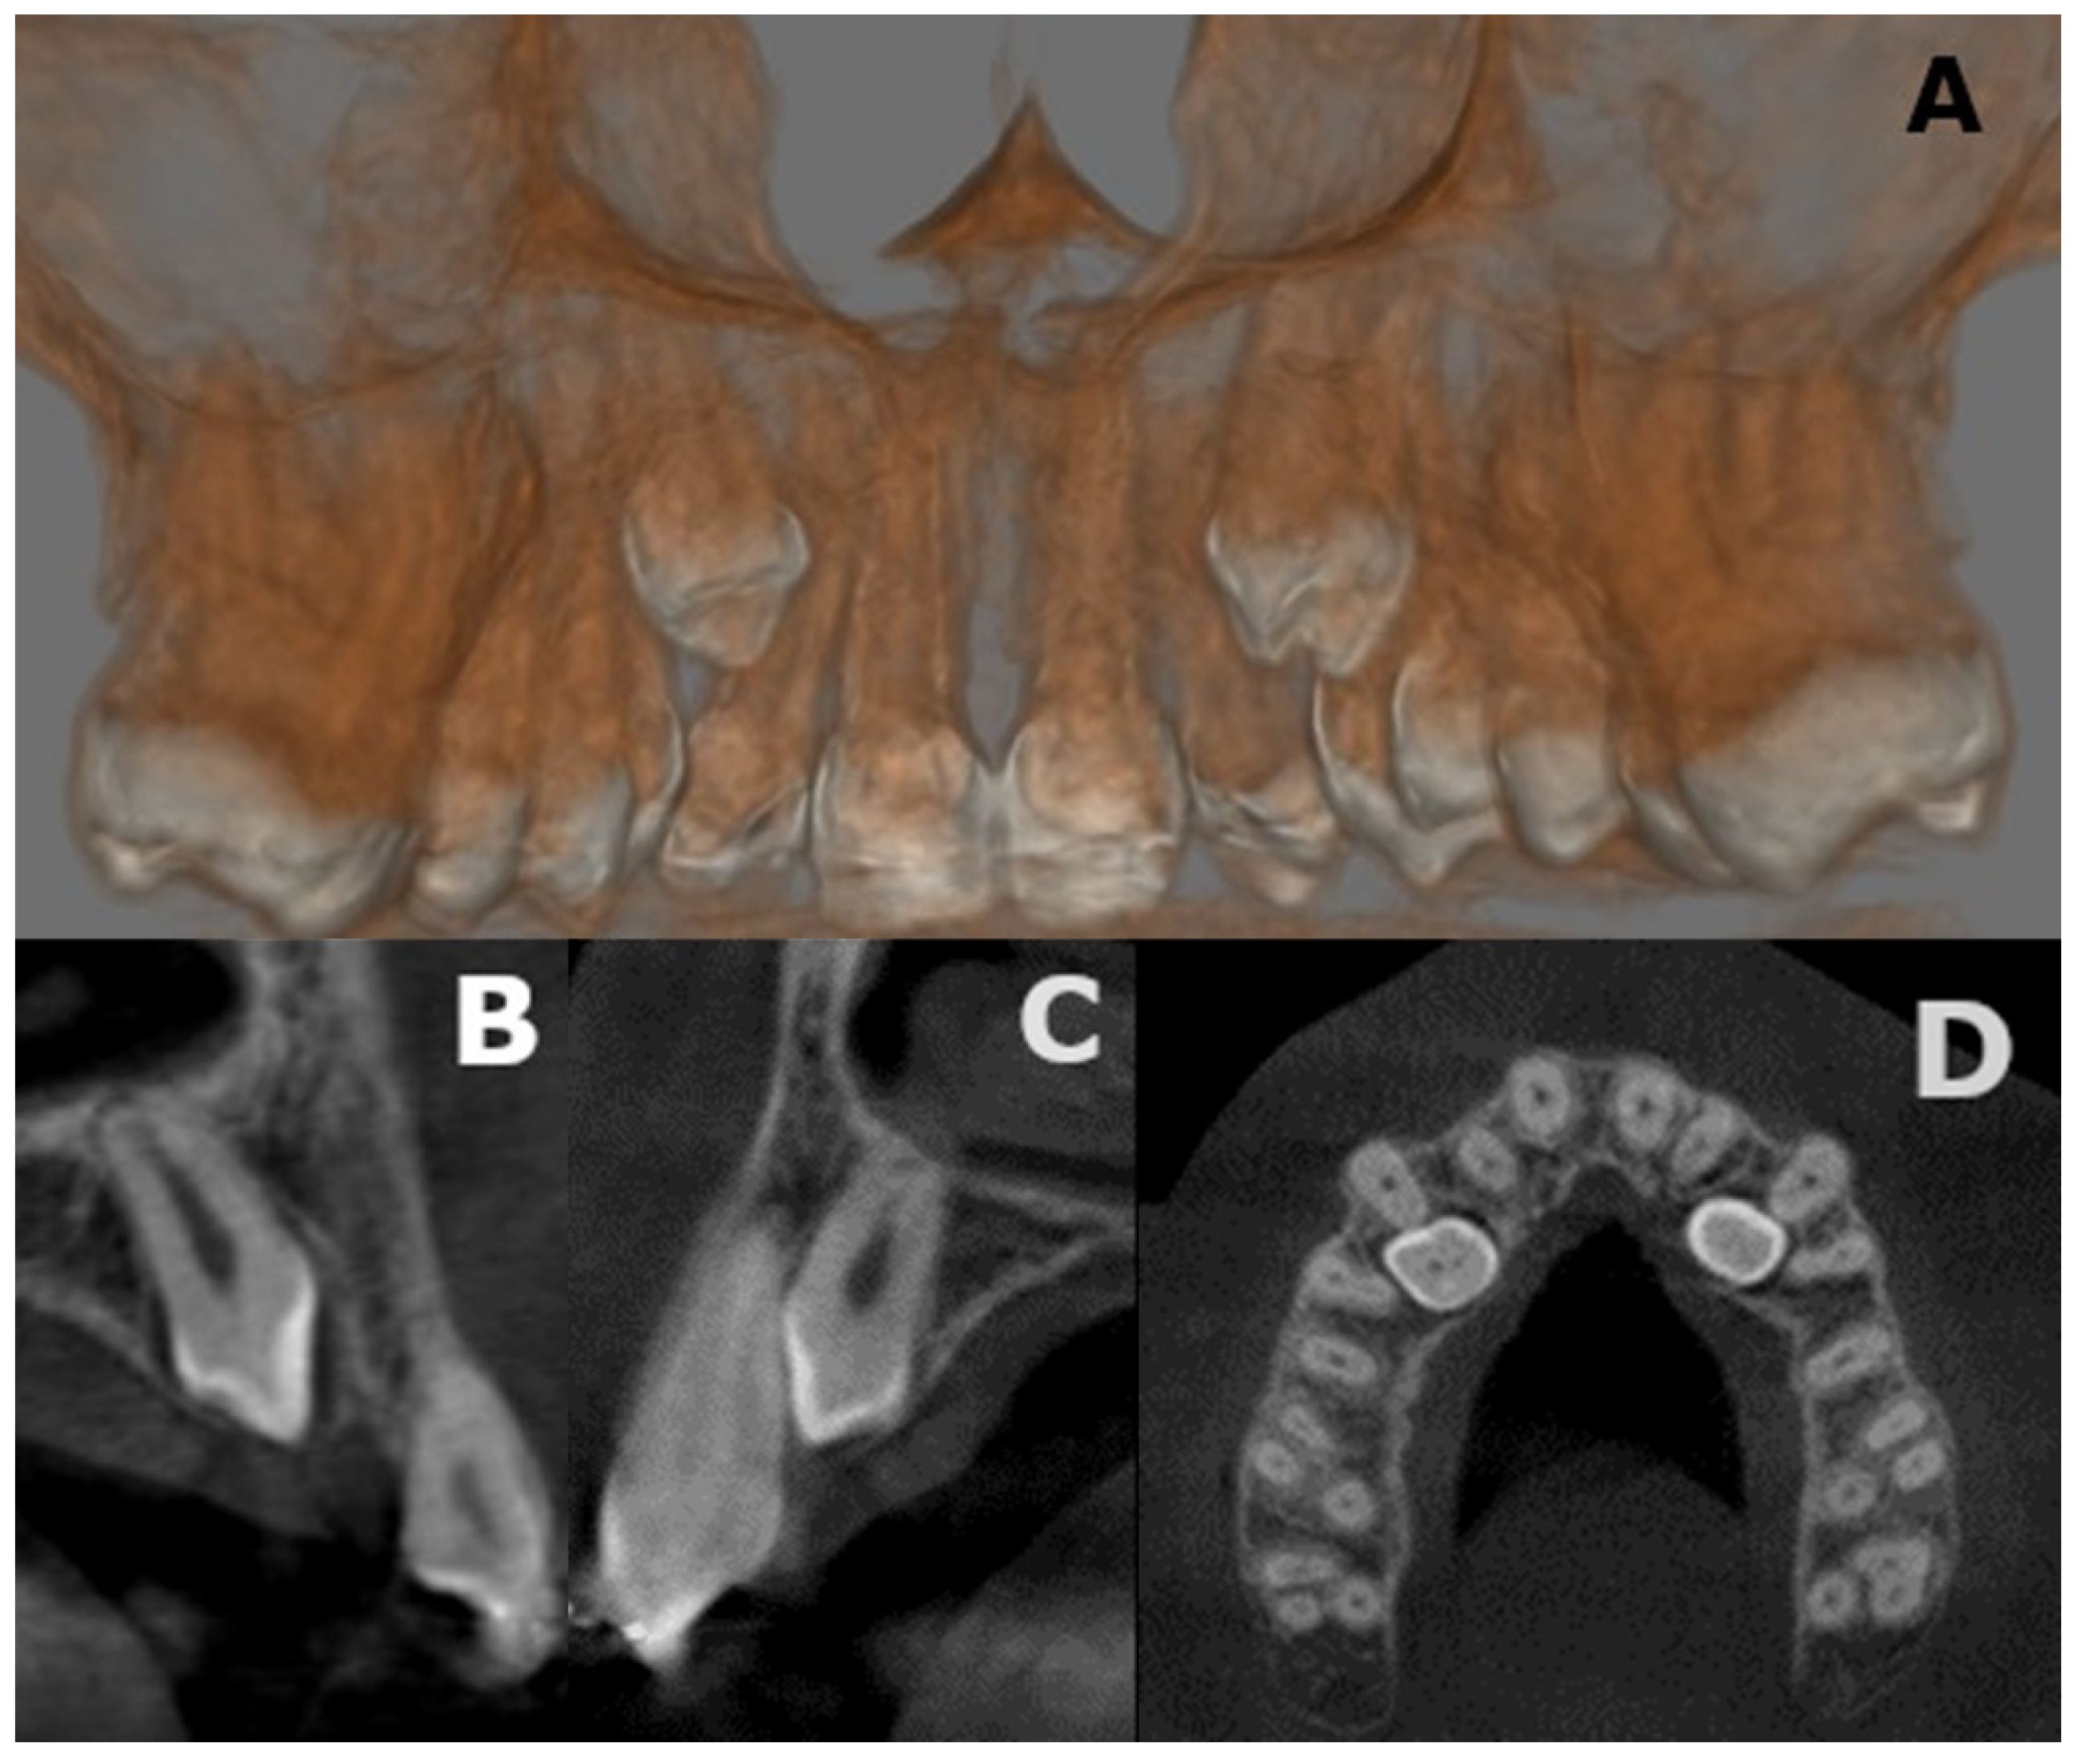

2.2. Considerations for Supranumerary Teeth Extraction